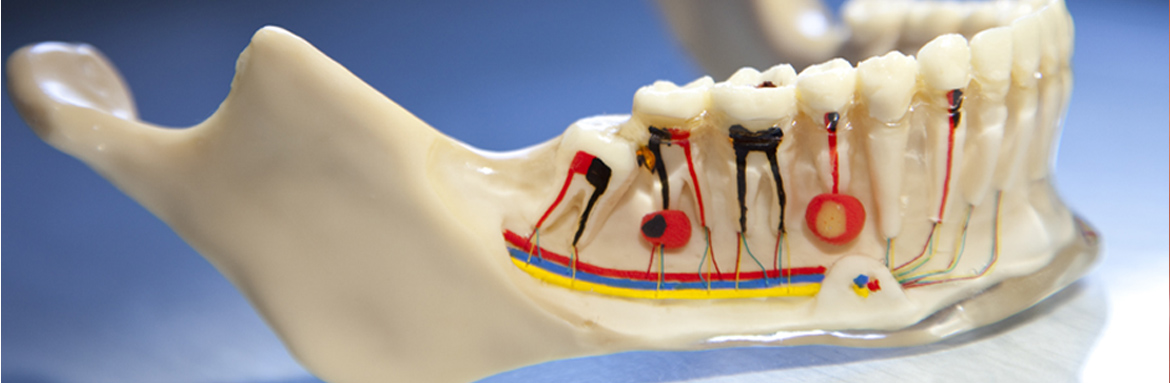

Ενδοδοντική Θεραπεία

Η ενδοδοντική θεραπεία,απονεύρωση,είναι απολύτως αναγκαία όταν η τερηδόνα έχει προχωρήσει σε τέτοιο βαθμό,ώστε να προσβάλλει τον πυρήνα του δοντιού,δηλαδή τον πολφό.Όταν υποστεί βλάβη ο πολφός και αρχίσει να νεκρώνεται,δημιουργούνται φλεγμονές και αποστήματα στο ακρορρίζιο που προκαλούν έντονο πόνο και πρήξιμο στον ασθενή.Για το λόγο αυτό η έγκαιρη παρέμβαση του οδοντιάτρου είναι απαραίτητη,όχι μόνο για την ανακούφιση των συμπτωμάτων,αλλά κυρίως για να σωθεί το δόντι.